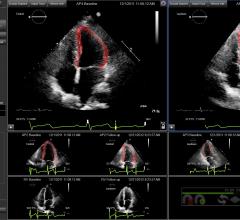

July 2, 2019 — Philips recently announced new advanced automation capabilities on its Epiq CVx and Epiq CVxi cardiac ...

June 19, 2018 — Clinical practice, along with guidelines and research, have shown that speckle tracking strain imaging ...

May 3, 2017 — Epsilon Imaging Inc. announced a research study using EchoInsight was presented at the American College of ...